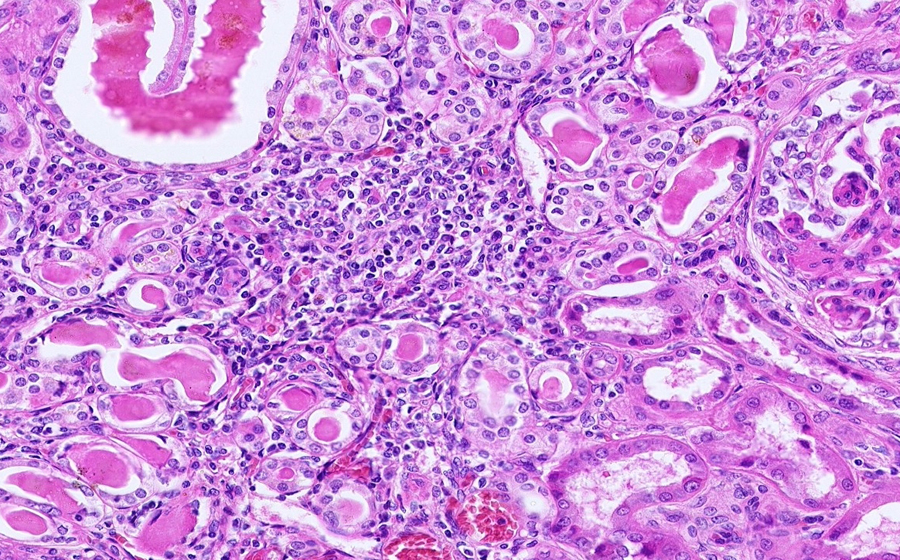

Slide 3: Glomerulonephritis - chronic

Histologic section of kidney from a patient with chronic glomerulonephritis. (click here to review normal tissue)

Image 2 - 12.5X

Slide 3 - Image 2